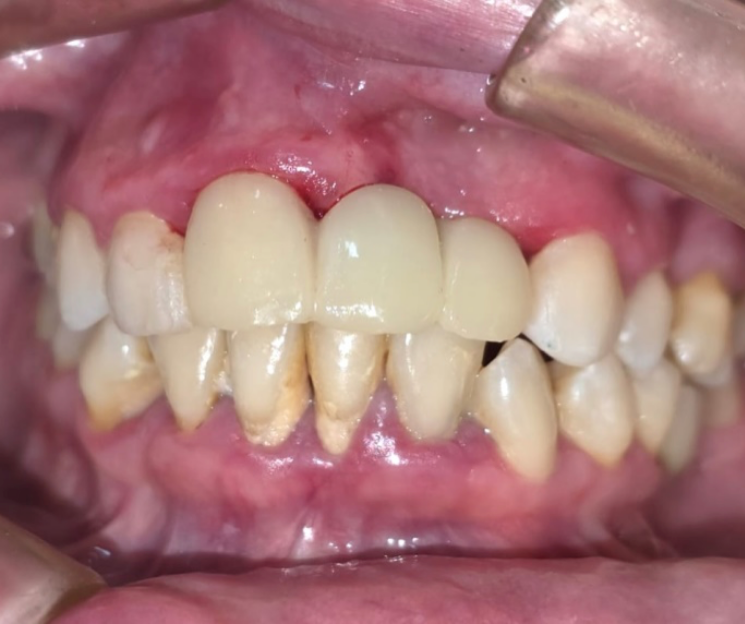

Clínica Dental especializada en la CDMX, Tijuana, Toluca, Cuernavaca, San Luis Potosí.  Colocamos  implantes dentales monofásicos de carga inmediata, también conocidos como implantes de una sola pieza. Somos una alternativa más rápida, estética y menos invasiva frente a los implantes tradicionales.

*Procedimiento: Colocación de implantes dentales monofásicos. A diferencia de los tradicionales (bifásicos), estos son de una sola pieza (tornillo y pilar integrados), lo que permite, colocar el implante y la prótesis provisional en una sola intervención o en un plazo de 3 días.

El tratamiento con implantes dentales está especialmente indicado para personas que han perdido una o más piezas dentales y desean recuperar su sonrisa a través de una solución fija, estable y definitiva, sin necesidad de prótesis removibles. Incluso aquellos pacientes que presentan poco hueso pueden ser candidatos, gracias a técnicas avanzadas que permiten trabajar con alternativas como la implantología monofásica. Además, es una excelente opción para quienes desean reemplazar prótesis removibles incómodas o poco estéticas, mejorando significativamente su calidad de vida, comodidad y confianza al sonreír.